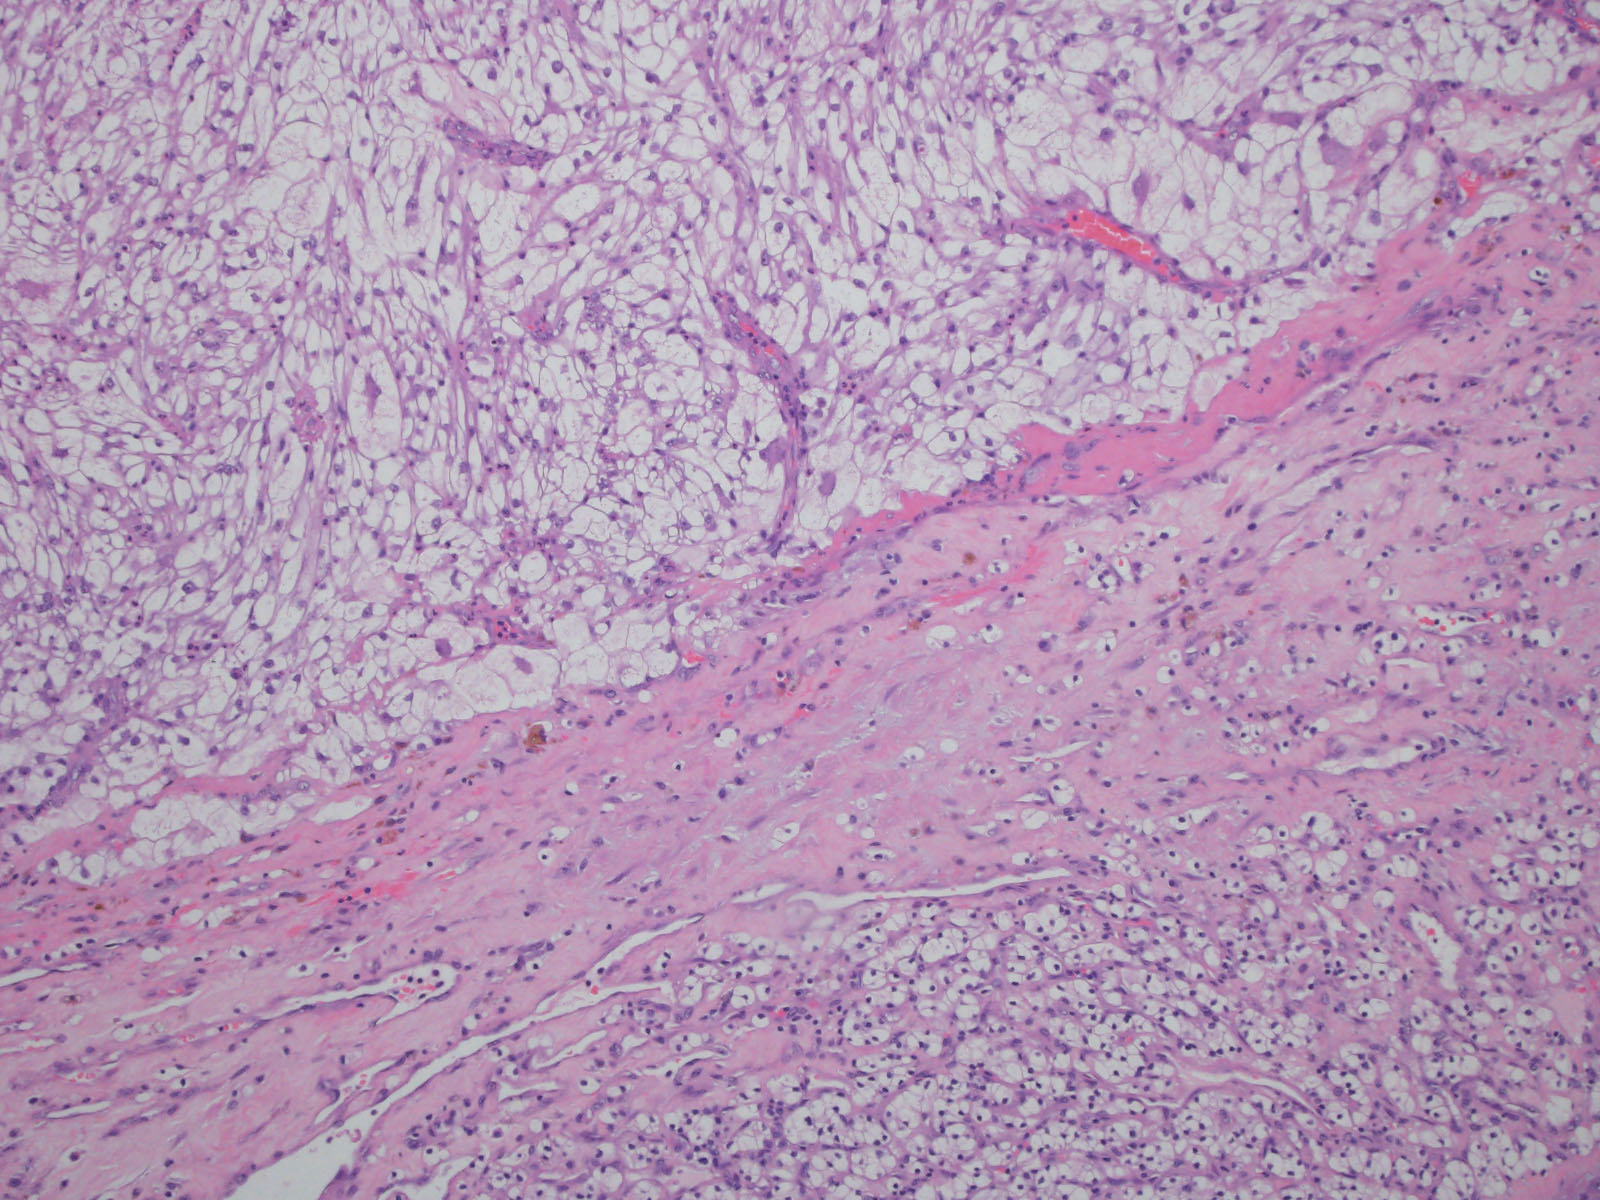

Consensus grade: Clear cell RCC

Show diagnosis by expert panel members| User | Diagnosis | Difficulty | Comment |

|---|---|---|---|

| Pathologist 1 | Clear cell RCC | Typical | |

| Pathologist 2 | Clear cell RCC | Typical | |

| Pathologist 3 | Renal cell carcinoma, unclassified | Not typical |

Could be a clear cell but not sure |

| Pathologist 4 | Clear cell RCC | Not typical | |

| Pathologist 5 | Clear cell RCC | Typical |

with sarcomatoid differentiation |

| Pathologist 6 | Clear cell RCC | Typical | |

| Pathologist 7 | Clear cell RCC | Typical |

sarcomatoid |

| Pathologist 8 | Clear cell RCC | Typical |

| Pathologist 9 | Insufficient tumor for diagnosis | Not typical | |

| Pathologist 10 | Clear cell RCC | Typical | |

| Pathologist 11 | Clear cell RCC | Not typical | |

| Pathologist 12 | Clear cell RCC | Not typical | |

| Pathologist 13 | Clear cell RCC | Not typical | |

| Pathologist 14 | Clear cell RCC | Not typical | |

| Pathologist 15 | Clear cell RCC | Typical | |

| Pathologist 16 | Clear cell RCC | Typical | |

| Pathologist 17 | Clear cell RCC | Not typical | |

| Pathologist 18 | Clear cell RCC | Not typical |